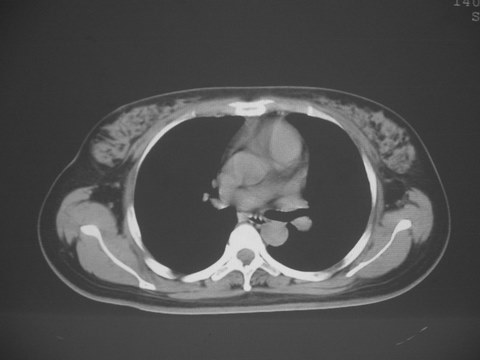

无意中发现右背部肩胛下缘半球状突起,无红,热,痛感觉。拍平片未见异常。ct发现右肩胛下角深层新月型软组织肿胀,ct值-50至15,大家看看是什么性质,来源,初步考虑来源于下后锯肿,考虑下后锯肌肿胀,可是病人无明确外伤史,也不疼痛

三、弹性纤维瘤影像

典型位于背部,在肩胛下角和胸壁软组织之间,肿瘤表面为菱形肌和背阔肌所被覆深部,紧邻肋骨和肋间肌,呈半圆形或扁豆状,宽基底与胸壁相交,边界比较清楚,相邻的肌肉和肋骨无侵蚀,部分病变与其表面的临近肌肉之间可受压呈弧形的脂肪界面,肿瘤周围软组织无水肿。

从mr表现可以推断ct影像,即肿块呈软组织密度,病灶内可出现脂肪密度的低密度影。